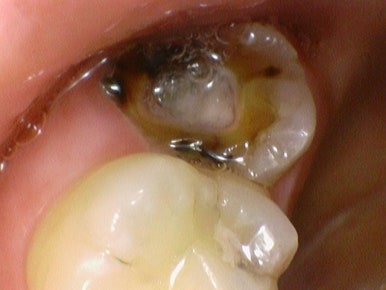

치료 전, 치료 중간 신경치료해야 할 만큼 깊은 충치를 보여드리기 위해 찍은 사진

저희 연세 예 감 치과는 다수의 구강카메라를 보유하여

치료해야 하는 치아의 이유를 환자분께 빠르게 직접 보여드리고 기록합니다.

필요한 경우에는 치료 중간중간 바로바로 구강카메라로 찍어서

깊은 충치를 보여드립니다.

충치치료, 레진, 크라운, 인레이, 발치 등 왜 그 치료를 해야하는지

과잉진료없이 객관적인 근거를 보여드립니다.